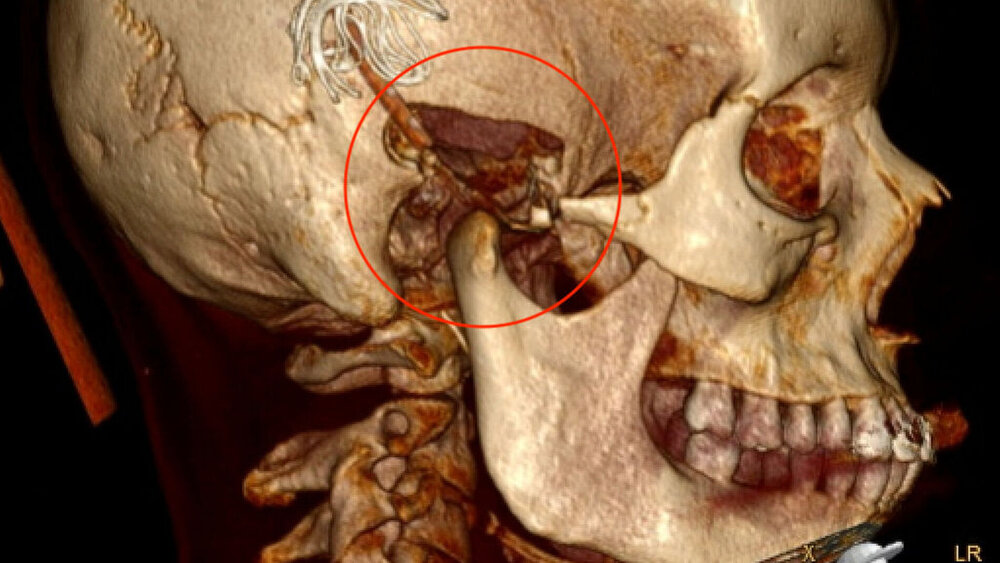

Zufallsbefund eines Riesenzelltumors bei langjähriger Bruxismus-Patientin